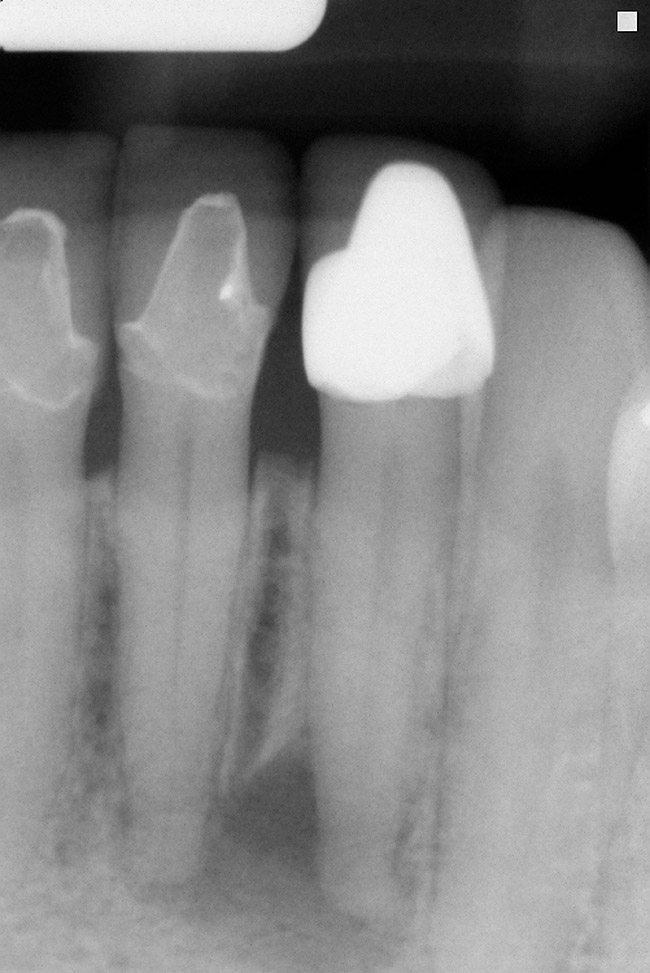

The decision to retain or extract a questionable tooth is one that occurs frequently in dental practice. There are many factors to consider when making this decision. Some situations are very straightforward (Figure 1) while others fall into a “gray” area of decision-making (Figure 2). This article will provide guidelines for determining whether to extract or retain a tooth when the decision is not so straightforward using structural, periodontal, endodontic, and esthetic criteria. Some teeth may involve only one of these areas, and some will involve various combinations of these areas. There are also other important factors to consider such as patient expectations, patient finances, and patient compliance, but these topics vary from patient to patient and should be discussed with each individual patient. While these topics are very important to the decision-making process, they are beyond the scope of this article.